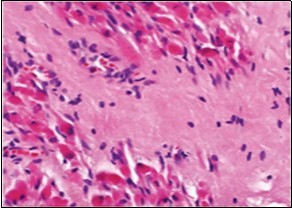

On microscopy, a collagen- rich, minimally cellular, fibrotic soft tissue nodule is exemplified which simulates a scar or conventional fibroma. The neoplasm is comprised of uniform, plump, fibroblastic or myo-fibroblastic cells encompassed in a collagen-rich stroma with infiltration and entrapment of skeletal myocytes 5, 6. Cogent histological examination depicts replacement of muscle fibres and muscle mass with fascicles of fibrous tissue comprised of mature fibroblastic cells, thereby conferring fibrosis 6. Figure 1, Figure 2, Figure 3, Figure 4, Figure 5, Figure 6, Figure 7, Figure 8.

Figure 3.Fibromatosis colli depicting fascicles of fibroblasts and myo-fibroblasts admixed with a collagenous stroma and extravasation of numerous red blood cells 10.

Fibromatosis colli  depicting   fascicles of fibroblasts and myo-fibroblasts admixed with a collagenous stroma and  extravasation of numerous  red blood        cells 10.